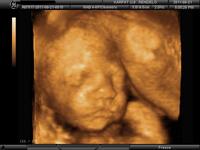

Hoztam én is uh képet Villőről :)

Ma délután voltunk, 26+1-n

Már közel egy kiló, 993 g. És van haja :)

Nagyon kis ficánka volt, a vizsgálat alatt vagy 5! teljes fordulatot tett... Jó nagy helye van még, a vizsgáló orvos szerint többedik gyereknél normális is, és ne is várjam nagyon, hogy befordul a 32. hét előtt... Remélem ez igaz, és nem lesz faros...